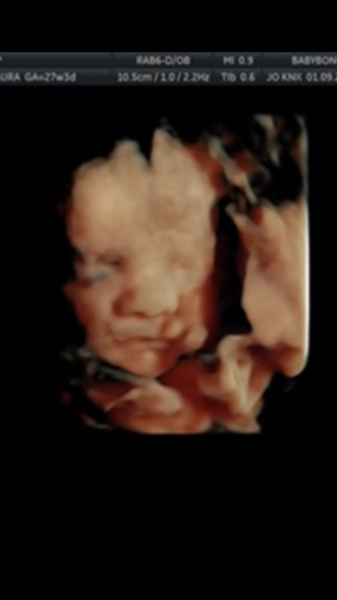

Kicks are still not strong enough for DP to feel but growth is normal.